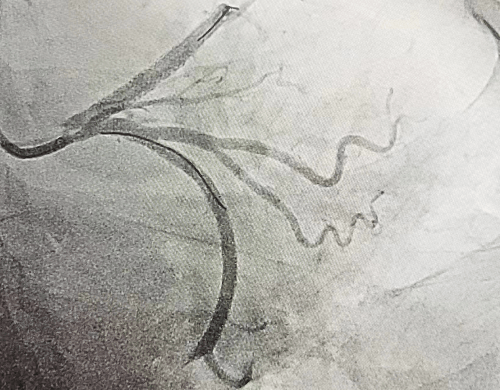

51歲的郭女士,因反復胸痛3天,加重2小時入院,入院后胸痛癥狀反復發(fā)作,檢查心電圖提示前壁導聯(lián)ST段明顯壓低,在此危急時刻心九科值班醫(yī)生陶醫(yī)生立即啟動導管室,心九科介入團隊行冠脈造影提示患者前降支近段99%狹窄,患者病情危在旦夕,遂立即行支架植入術解除冠脈狹窄,患者生命得以及時救治。

冠脈手術前